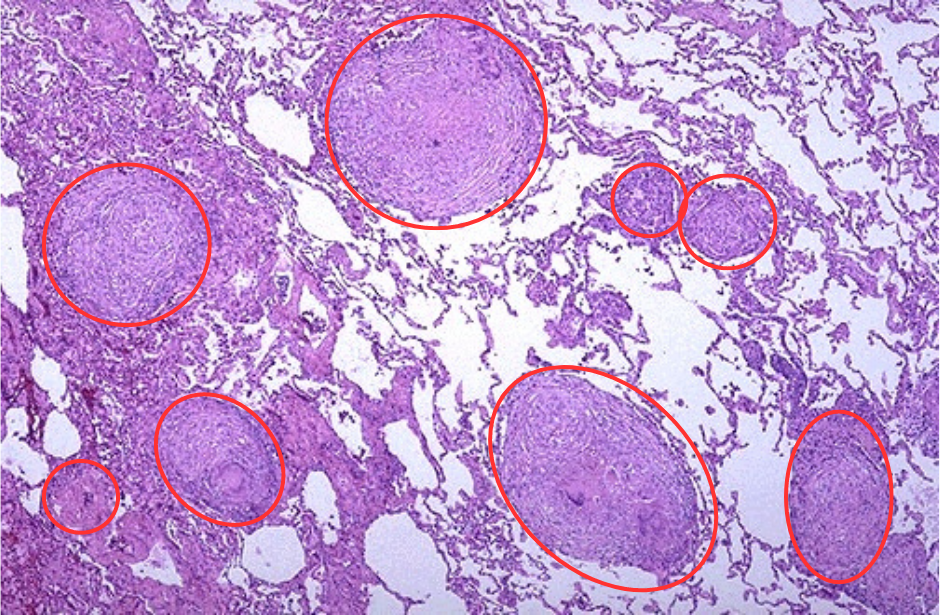

The most well-known method by which tuberculosis manipulates our immune system is through macrophages. They are the primary defense against invaders, the clean-up crew, and the primary tuberculosis target. The bacterium prefers to be engulfed by lung macrophages, which create a dense clump of cells that hides the bacterium for a long time, sometimes even years.